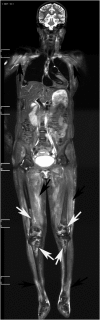

Results: STIR-WBMRI detected osteonecrosis in 15 (11.6%) patients. 38 joints were affected (mean, 2.5 per patient; range, 1-5 joints). Of the 38 joints affected by osteonecrosis, 33 had no clinical symptoms. Among the 12 patients who underwent regional MRI, STIR-WBMRI detected all 10 osteonecrotic sites seen on the regional MRI. The location, shape and size of the osteonecrotic lesions revealed on regional MRI were in accordance with those displayed on STIR-WBMRI. Of the 15 patients with osteonecrosis, 6 performed routine radiography of the affected joints and revealed no osteonecrotic lesions. Follow-up WBMRI detected new osteonecrosis in two patients whose first WBMRI revealed that there was no osteonecrosis in any skeleton.

Conclusion: In addition to displaying muscle inflammation, STIR-WBMRI can efficiently detect early multifocal osteonecrosis in the whole bodies of patients with PM/DM. Advances in knowledge: In patients with PM/DM, WBMRI which takes 12-15 min can display muscular involvement and detect early multisite osteonecrosis in the whole body at the same time. Osteonecrotic lesions revealed by WBMRI are in accordance with those displayed on regional WBMRI.